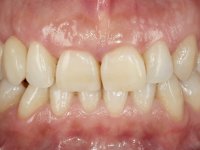

Female patient, 43 years old, non-smoker. Showed an edentulous space in the upper right canine area, resulting from tooth 1.3 impaction. The space had a mesio-distal diameter reduced to the normal size of the upper canine. This is consistent with the presence in the arch of the deciduous canine up to two years ago). Orthopantomography allows clearly view of tooth 1.3 impaction.The patient has a thick gingival phenotype and tolerable oral hygiene.

The proposed treatment results from the limitations imposed by the patient, who refused an orthodontical pull of the canine into the edntulous space, and was unwilling to extract the impacted canine and place an implant in the zone of 1.3. Thus, the confection of a Maryland Bridge was proposed, with a Zr infrastructure and two retainers. The mesial retainer would be bonded to the palatal face of the tooth 1.2 and the distal retainer was to be bonded to the palatal wall of tooth 1.4.